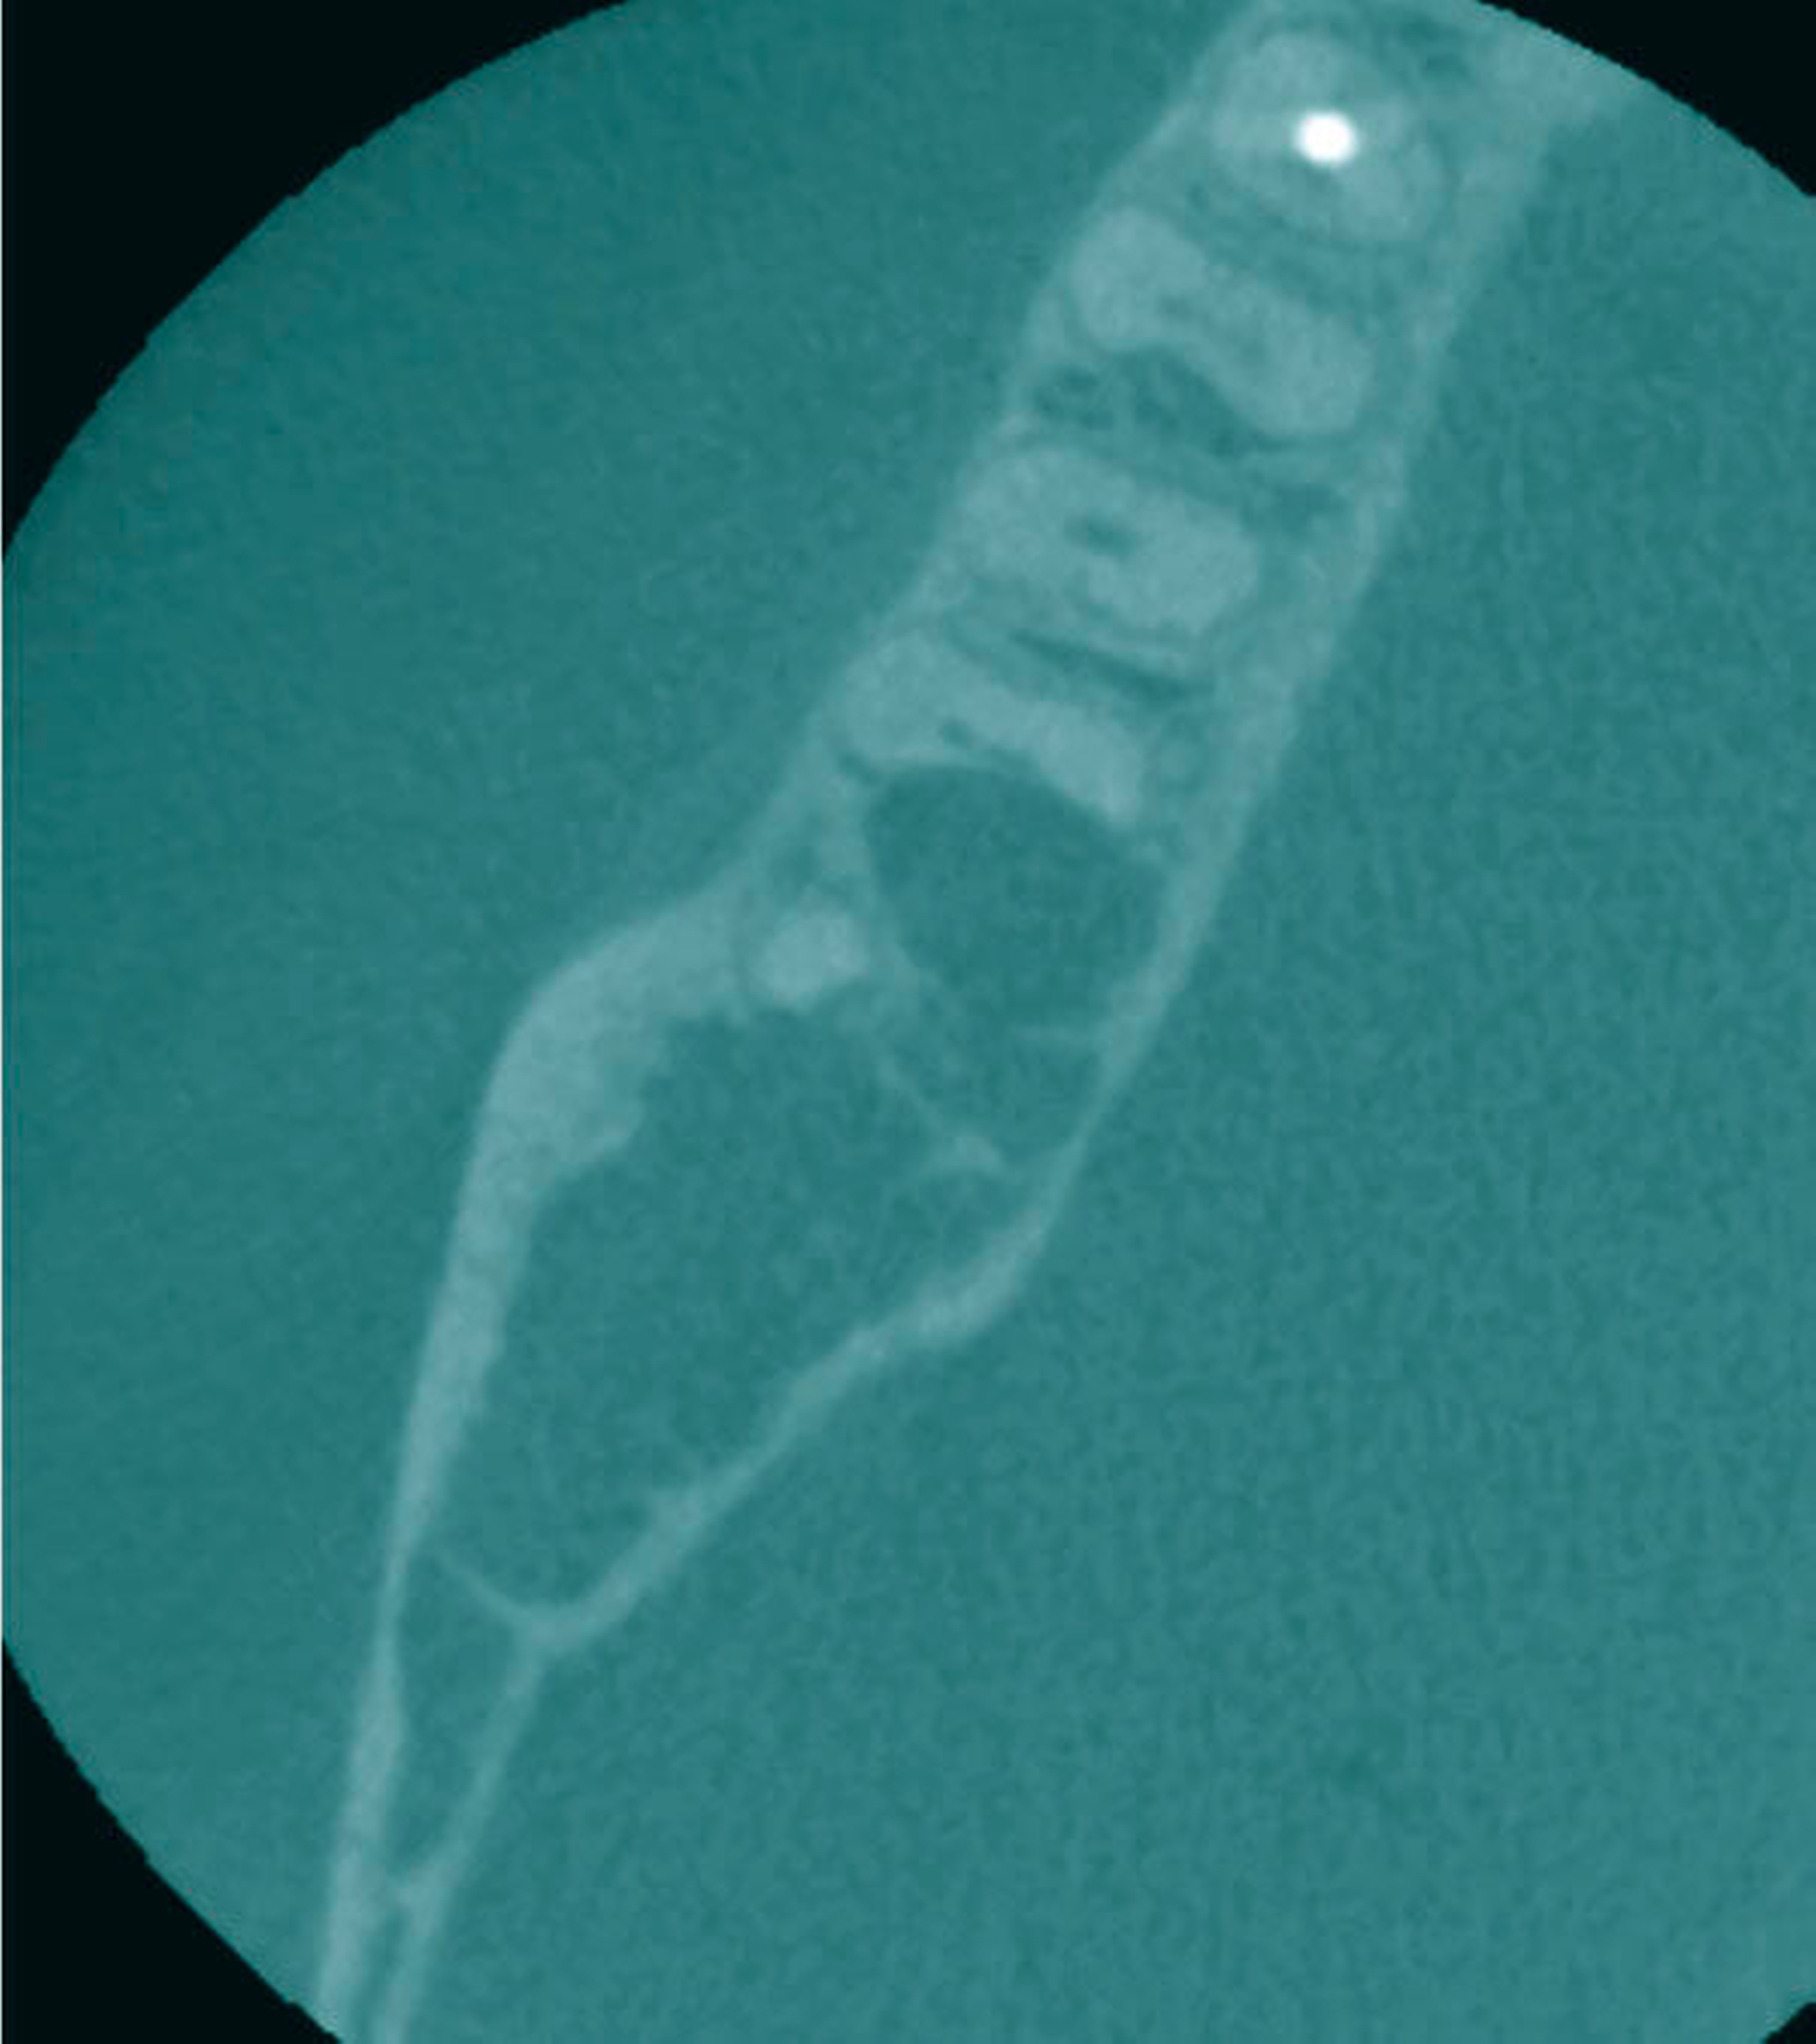

Auf der alio loco durchgeführten Panoramaschichtaufnahme (Abbildung 1) war eine ausgeprägte, zystische Raumforderung mit einer Ausdehnung von Regio 46 bis Regio 48 zu erkennen. Klinisch zeigten sich keine Sensibilitätsstörungen im Bereich des Nervus alveolaris inferior. Die Vitalitätsprüfung der Zähne 46 bis 48 fiel positiv aus, es bestand auch keine Perkussionsempfindlichkeit (Abbildung 2). Zahn 48 fiel durch eine drittgradige Lockerung auf. Auf Palpation entleerte sich kein Pus. Die anschließend durchgeführte Digitale Volumentomografie (Abbildung 3) zeigte einen invasiv wachsenden, teils honigwabenähnlichen, zystischen Befund des rechten Unterkiefers mit einer Ausdehnung in den Canalis mandibulae sowie in Teile des aufsteigenden Unterkieferasts. Darüber hinaus ließen sich Wurzelresorptionen der Zähne 47 und 48 eruieren.